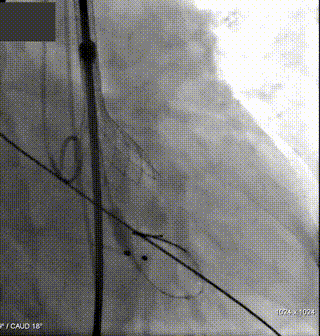

2.主动脉根部造影,示双侧冠脉灌注良好;

4.180次/分快速起搏下以TaurusAtlas 22mm 球囊进行预扩张,扩张同时造影示轻微腰征,无造影剂渗漏,被推开的左冠瓣瓣叶未累及左冠开口,左冠显影明显;

5. 根据术前评估及球囊预扩情况,选择沛嘉TaurusElite AV26号瓣膜进行植入,在120次/分快速起搏下释放瓣膜,第一次释放至工作位发生下滑;

6. 回收后进行重新定位释放,释放完毕后超声评估示平均跨瓣压差15mmHg,超声、造影评估示中量瓣周漏、少量瓣中漏,瓣膜整体下滑明显,遂行瓣中瓣策略;